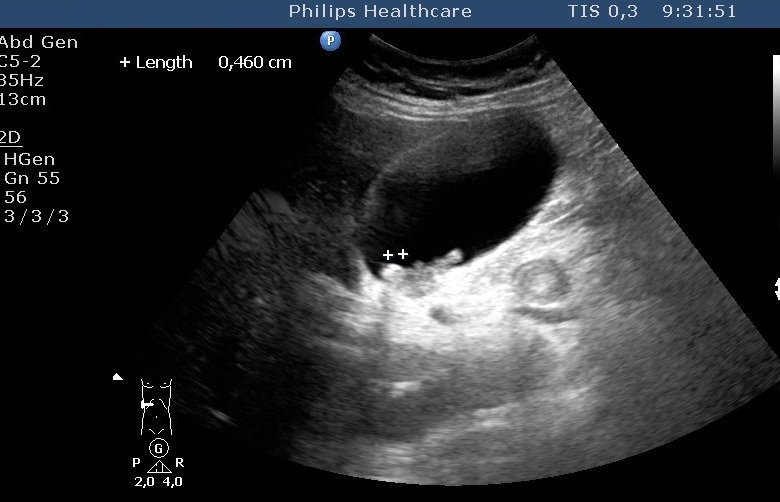

Figure 47: Spleen cyst, US

The spleen cysts occur less frequently then the liver cysts, their morphological appearence is similar to that of the liver cysts (homogeneous, cystic content, sharp contour, thin wall, sometimes some thin septa). Most of them is detected only accidentally. It has a therapeutic consequence if its size increases resulting symptoms for the patient by the compression of the sorrounding tissues (Figure 47, 48).